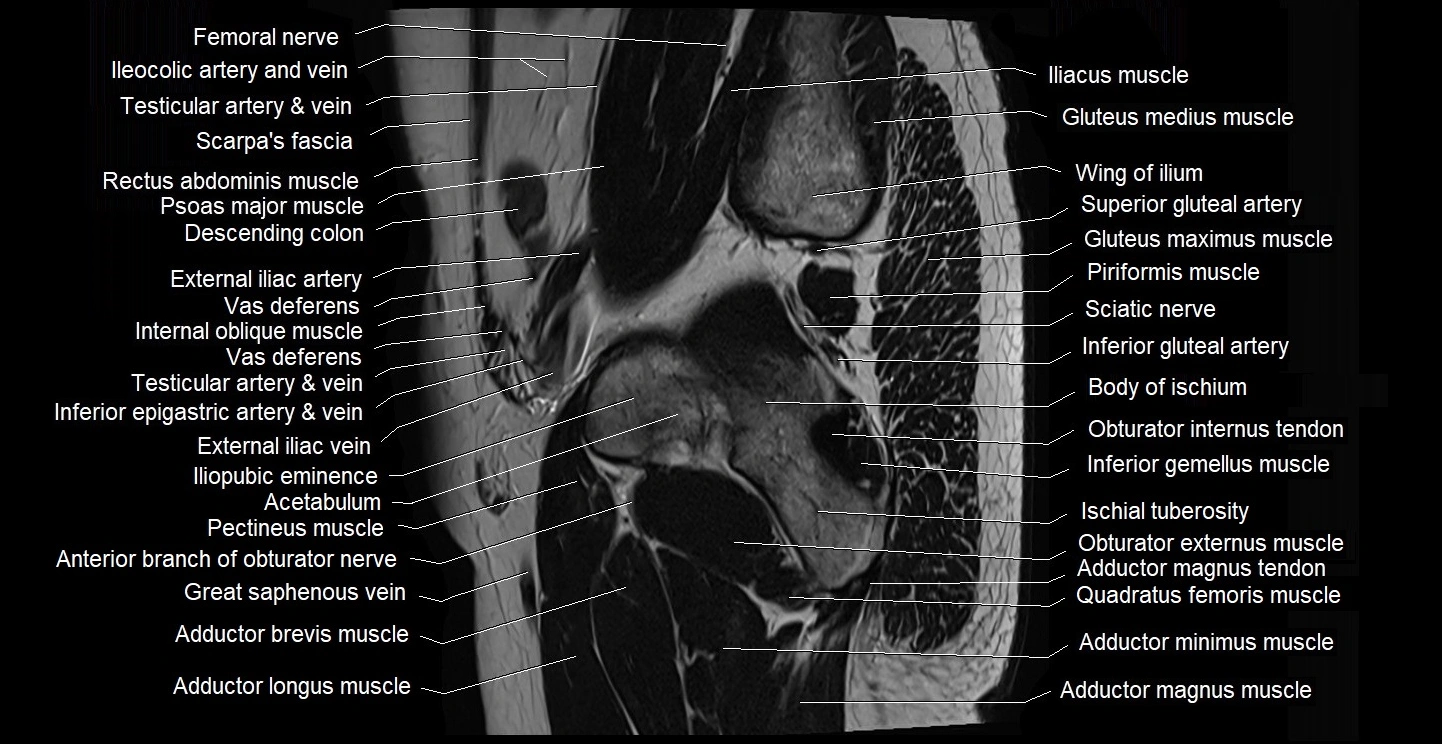

- Adductor brevis muscle

- Adductor longus muscle

- Adductor magnus muscle

- Adductor minimus muscle

- External iliac artery

- External iliac vein

- Gluteus maximus muscle

- Gluteus medius muscle

- Greater trochanter

- Iliopubic eminence

- Inferior gemellus muscle

- Inferior gluteal artery

- Lumbosacral trunk

- Obturator externus muscle

- Obturator internus muscle

- Obturator internus tendon

- Pectineus muscle

- Piriformis muscle

- Posterior femoral cutaneous nerve

- Quadratus femoris muscle

- Sciatic nerve